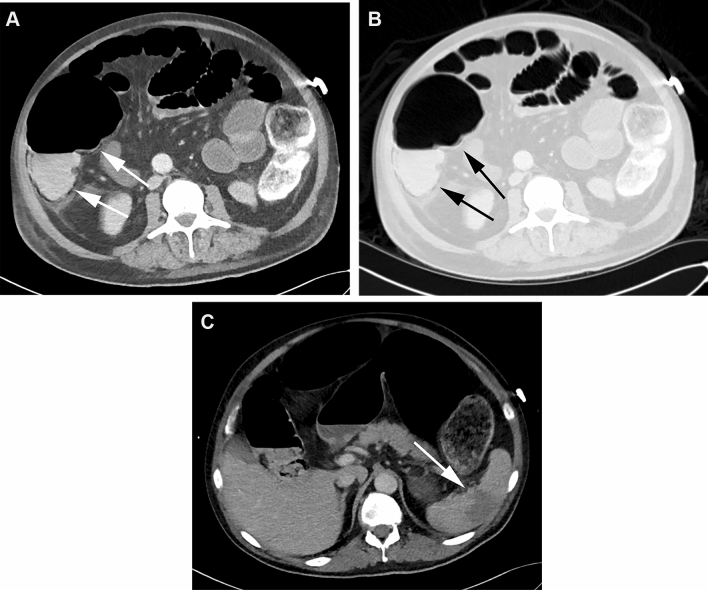

Fig. 2.

CT in the soft tissue (a) and lung window (b) of a 70-year-old male patient with PI in the colon (arrows) and distension of the small bowel and colon. In addition, perfusion inhomogeneities indicating ischemia in the spleen were found (c, arrow). The AST blood level was 80 IU/L (normal values 7–37 IU/L), the blood lactate level was 8.1 mmol/L (normal values 0.5–2.2 mmol/L). The patient died one day after CT